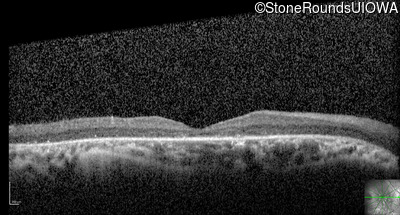

Optical Coherence Tomography - Right - 20/63 +2

Exemplar / OCT Stack